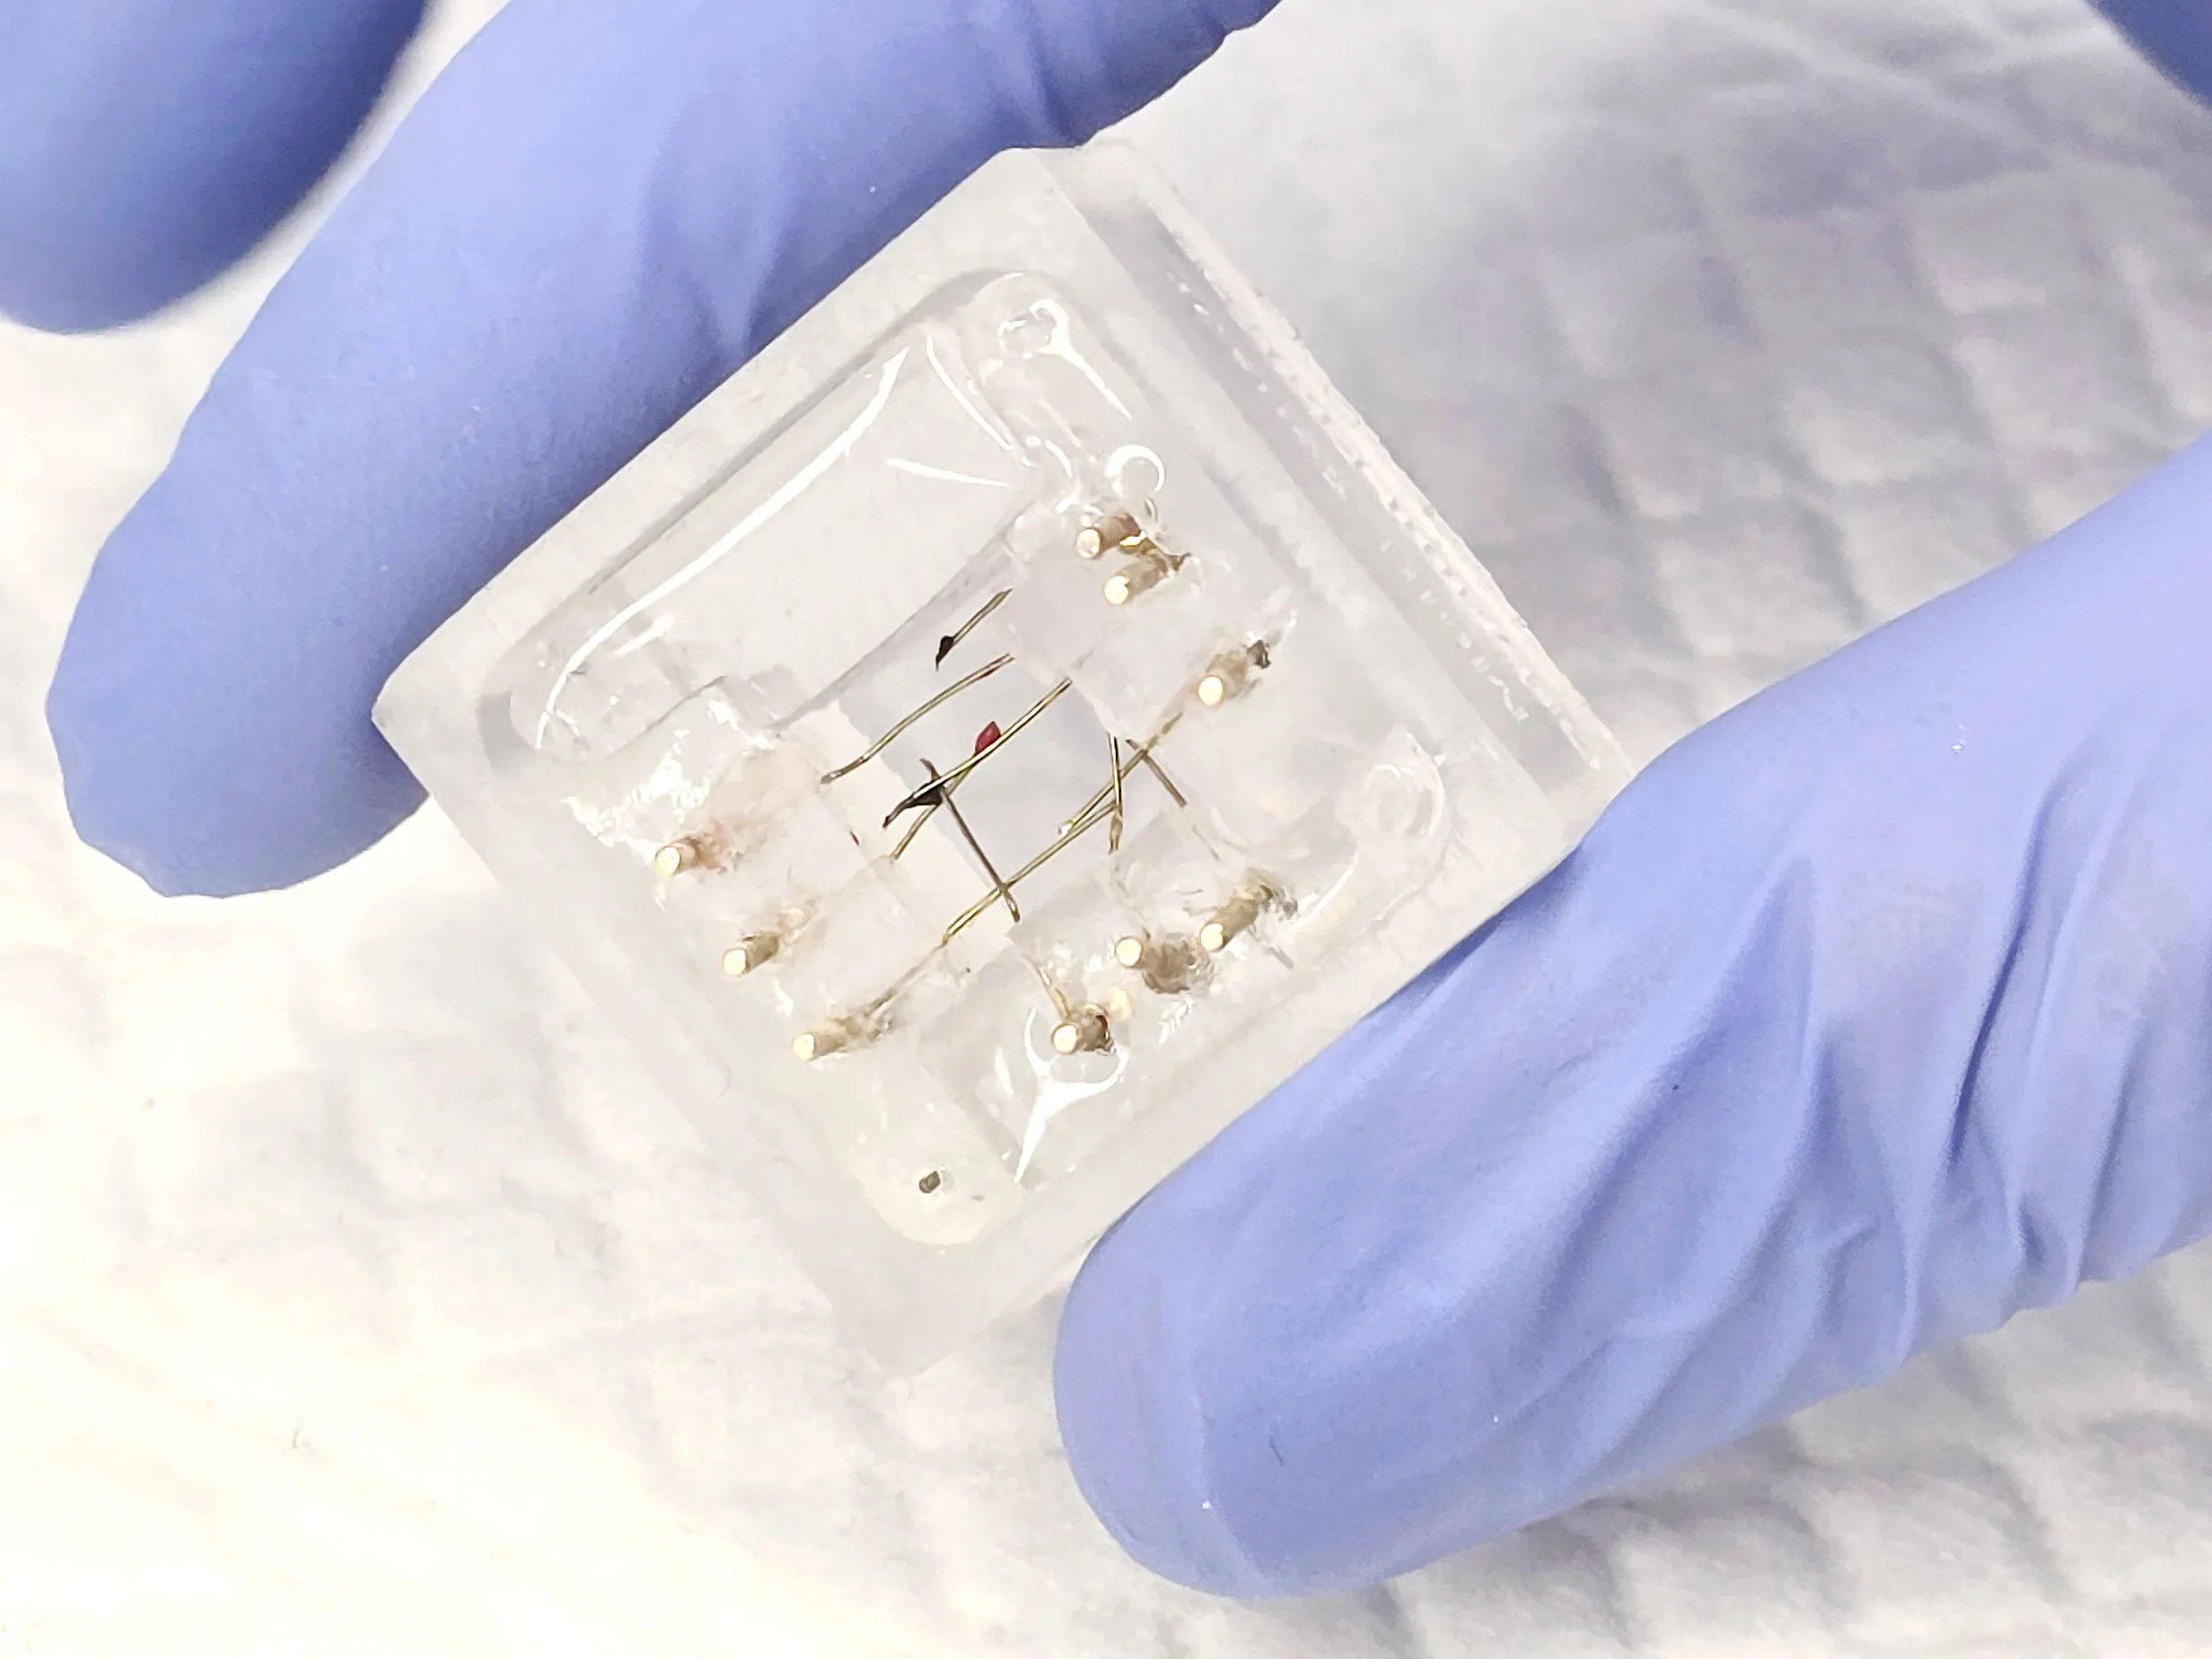

La nueva plataforma es un dispositivo de goma de silicona que puede plegarse alrededor de una estructura bioimpresa. El prototipo sostiene una matriz comercial de electrodos 3D para capturar señales eléctricas, y también posee otros electrodos que miden la resistencia eléctrica, revelando la permeabilidad de las células a varios medicamentos. Un modelo de software 3D personalizado puede adaptar el diseño del origami y los electrodos para que los sensores se coloquen en ubicaciones específicas del objeto bioimpreso.

Los científicos probaron su dispositivo en cúmulos bioimpresos de células cerebrales. El equipo también cultivó una capa de células en el origami que imitaba la barrera hematoencefálica, una capa celular que protege el cerebro de sustancias indeseables en la sangre. Al plegar esta combinación de origami y células sobre las estructuras bioimpresas, Maoz y sus colegas pudieron monitorear la actividad neuronal y observar cómo su barrera hematoencefálica sintética podría interferir con medicamentos destinados a tratar enfermedades cerebrales.